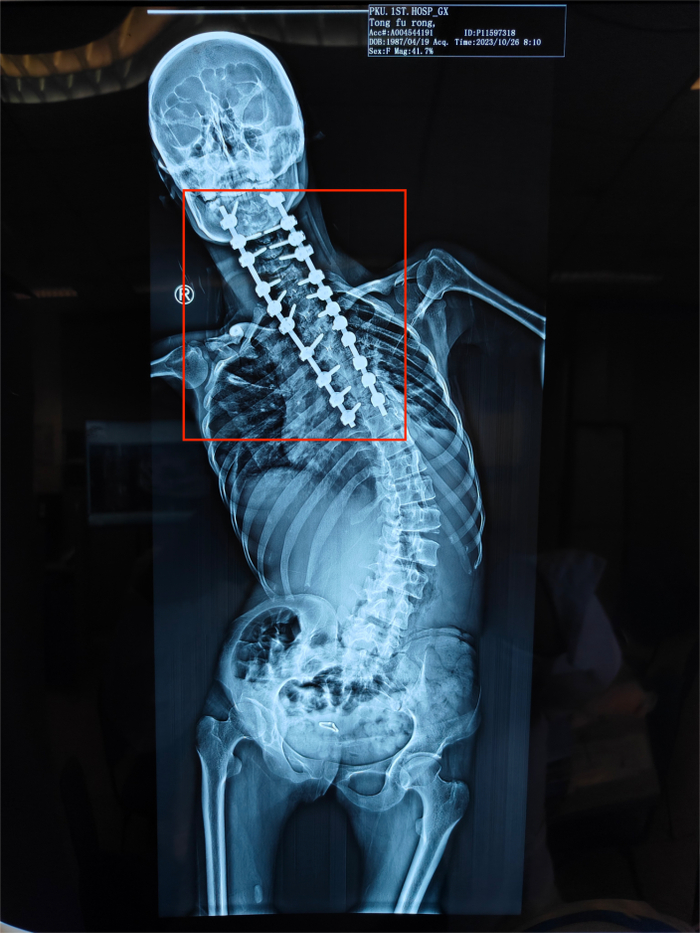

这是一场“天花板级别”的手术。童福容的背部被整个打开,暴露出神经密布的脊柱,22颗螺钉被依次植入侧弯的椎体里,加上4根筷子粗的钛棒,她反向折叠180度的身体就这样被拉直了。

童福容第一次手术后,红色部分为固定脊柱的螺钉

受访者供图

中午十二点左右,王宇走进手术室,进行手术最关键的部分。他借助导航系统将22颗椎弓根螺钉依次植入到患者脊柱并进行固定,然后再进行植骨融合和缝合操作。手术室里不断发出钉子与骨头碰撞后的清脆声音。